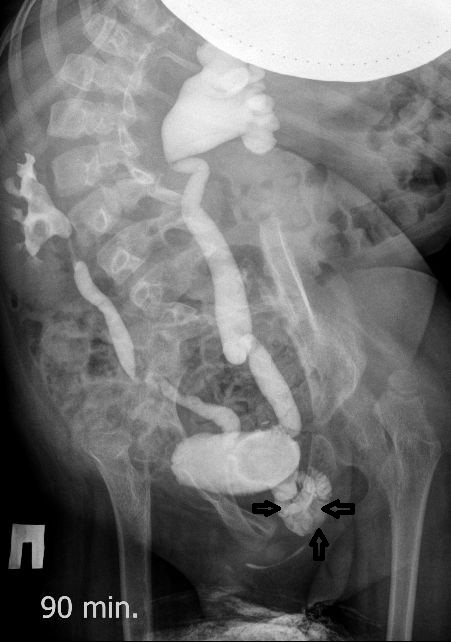

Всё верно, только что вот это ?

DX0001.jpg

И что законтрастировалось на экскреторных урограммах около мочевого пузыря?

DX0004.jpg

Стриктура уретры с расширением ее проксимального отдела?

Если честно, и я изначально не совсем понял, где находится конкремент (а это конечно же конкремент), локализованный на урограммах. При первичном исследовании на УЗИ его я не видел (либо он спрятался за тенью конкремента мочевого пузыря, либо я обрадовался редкой находке конкремента такого размера в мочевом пузыре - 2.5 см, и не посмотрел что ниже). Тем не менее при ретроспективном анализе архивированных сонограмм, как мне кажется, он попал в один из сканов, м.б. не совсем чётко.

И всё -же, где конкремент :?:

Возможно, в дивертикуле либо в нижней трети мочеточника..

Верификация:

Выдержка из протокола операции- "...вскрыт мочевой пузырь, обнаружен камень 4 х 3х 2.5 см, плотный, удалён. При дальнейшей ревизии мочевого пузыря обнаружен вколоченный камень в шейке мочевого пузыря и в уретре, удалён камень 2 х 1.5 х 1.5 см. При осмотре устья левого мочеточника - последний зияет, мочеточник расширен до 1 см, учитывая расширение мочеточника, проведена антирефлюксная пластика по Грегуару..."